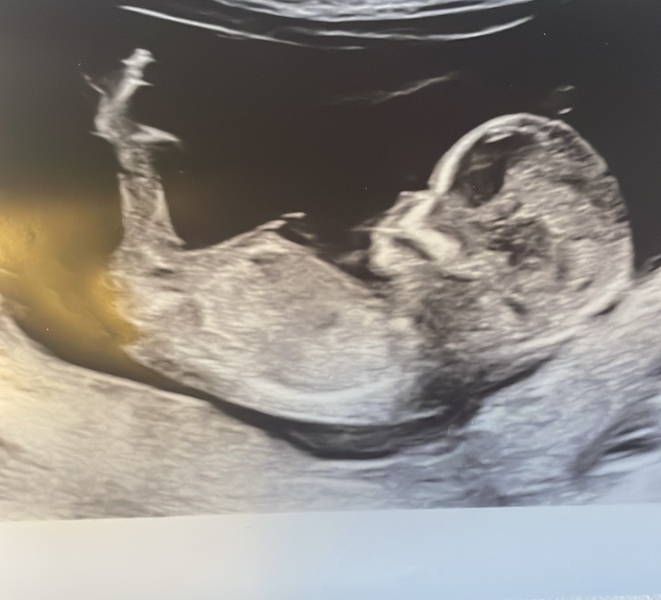

Nub? Is there no nub? Anyone got any guesses

Hello! I am expecting a 3rd (yikes!) and none of mine of my husbands family have girls so there is a lot of pressure. We are going to find out in a few weeks but just wanted to see what people thought? I’m happy with either but feeling the pressure to produce a girl 😬🫣. I have A LOT of photos. Asked for 2 but got 5 so I’ll post them all 😂